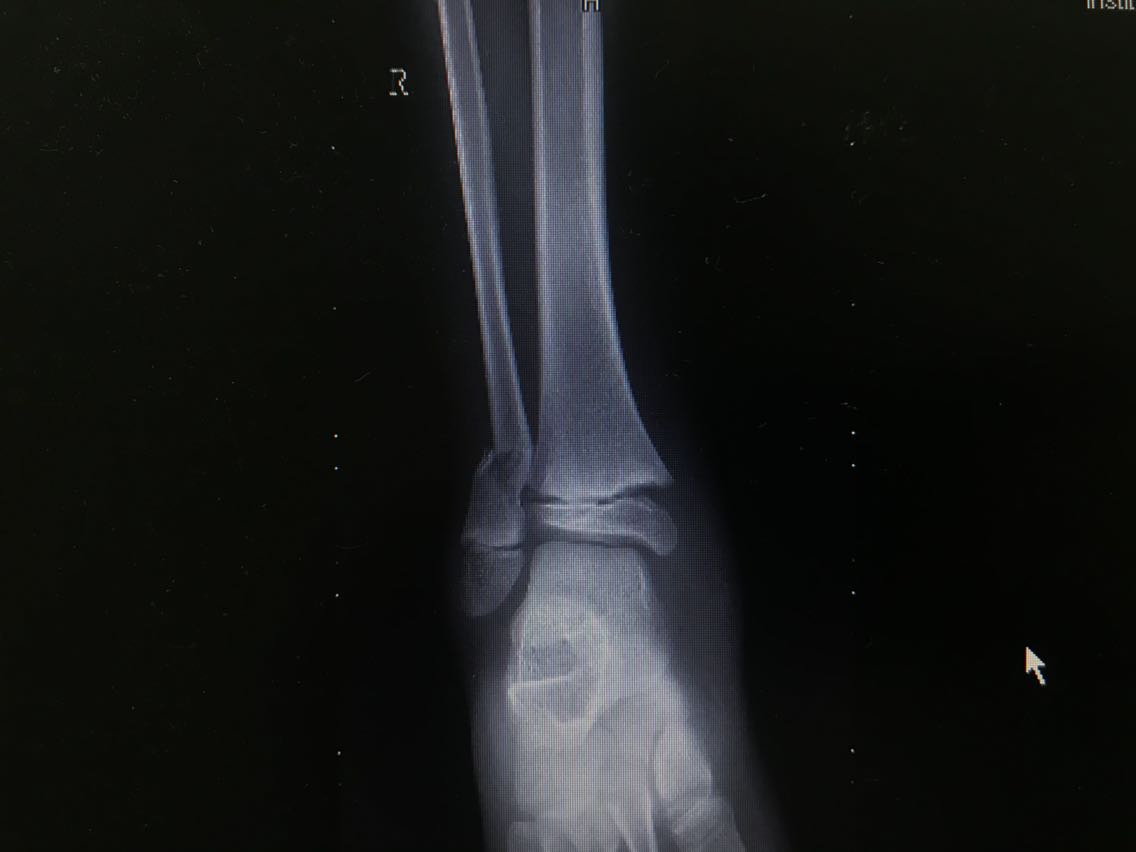

患者男性,10岁。 主诉:摔伤致右小腿疼痛,活动受限3+天 现病史:患者3+天前从高处摔下,高度约6米,摔下后右足着地。患者自述右侧小腿下段疼痛,可以耐受,意识清楚,呼之能应,无呕吐其他不适。右小腿肿胀、疼痛伴活动障碍,局部皮肤有明显青紫,无破损、流血等。遂至当地医院就诊,未予特殊处理,建议上级医院就诊。遂就诊于我院急诊科,行X线检查示:右侧腓骨下段骨折,断端稍成角、迂曲,右外踝关节间隙稍增宽,周围软组织肿胀。CT检查示:右侧腓骨下段骨折,断端稍成角、迂曲,右外踝关节间隙稍增宽,右胫骨干骺端与骺板间隙稍增宽,周围软组织肿胀。经我科医师会诊,以“右腓骨下段骨折”收入我科。患者自受伤以来精神睡眠可,食欲可,大小便正常,体重未见明显变化。 既往史无特殊。

查体:右小腿远端、足部肿胀明显,局部皮肤可见青紫,未见破损,右小腿远端皮温低,压痛不明显,桡动脉、足背动脉搏动可,右踝节活动受限,右足趾感觉、血运、活动正常,其余肢体未见明显异常。 辅助检查: X线检查,示:右侧腓骨下段骨折,断端稍成角、迂曲,右外踝关节间隙稍增宽,周围软组织肿胀。请结合临床及其它检查。右侧胫骨未见确切错位骨折征象。 CT检查,示:右侧腓骨下段骨折,断端稍成角、迂曲,右外踝关节间隙稍增宽,右胫骨干骺端与骺板间隙稍增宽,周围软组织肿胀。请结合临床及其它检查。